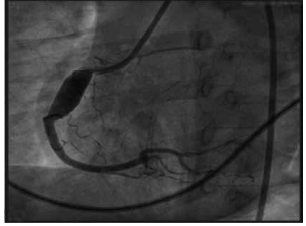

Paciente de 1 mês de idade foi admitido em Unidade de

Terapia Intensiva, acompanhada de cuidadora de abrigo,

devido à piora da cianose. Mãe drogadita perdeu guarda

dos 6 filhos. A saturação na Unidade manteve-se estável,

ao redor de 84%, sem insuficiência cardíaca congestiva,

em uso de propranolol; foi acompanhado no ambulatório

até os 2 anos de idade e realizada intervenção cirúrgica

cardíaca. Com base nos seguintes exames complementares, quais seriam, sucessivamente, a cardiopatia congênita provável, a cirurgia realizada aos 2 anos de idade

e a cirurgia atual para a qual foi convocada?

(Arquivo pessoal; imagens usadas com autorização)